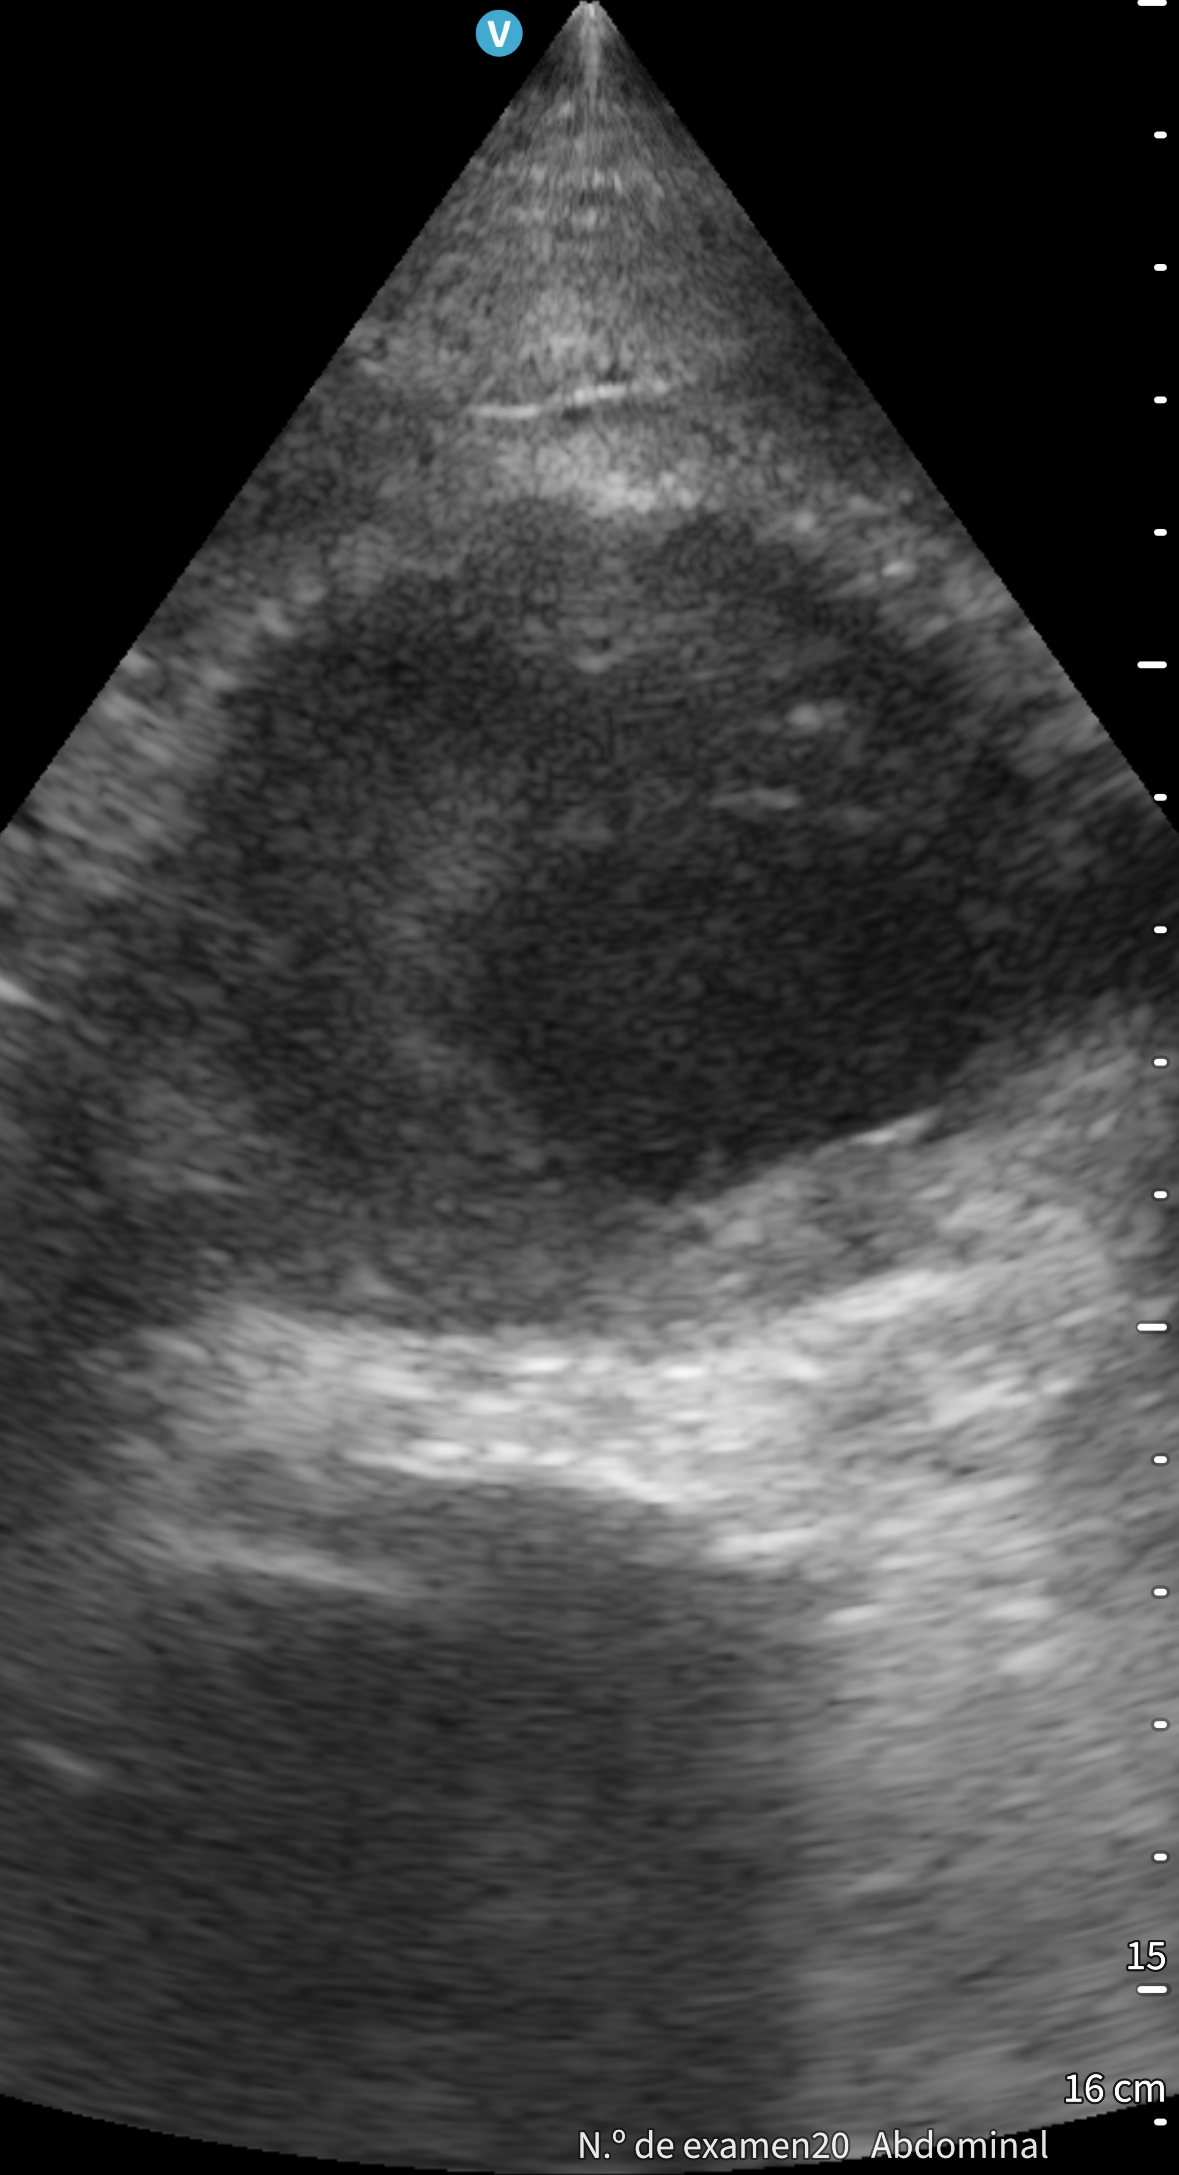

Tras finalizar una sesión de diálisis desarrolla hipotensión sintomática y dolor lumbar. A su llegada a urgencias presenta TA 60/40 mmHg, palidez mucocutánea y exploración abdominal anodina. Se inicia fluidoterapia. Ante la sospecha de rotura aneurismática se realiza ecografía a pie de cama, que muestra aneurisma de aorta abdominal con trombo mural irregular y luz permeable reducida, sin signos de rotura, permitiendo descartar una emergencia tiempo-dependiente. El angioTAC urgente confirma la ausencia de disección o extravasación, aunque evidencia crecimiento aneurismático respecto a estudios previos. Analítica sin anemia aguda, ligera leucocitosis y troponinas discretamente elevadas sin ascenso dinámico. Evoluciona favorablemente con recuperación tensional y resolución del dolor.

La ecografía clínica a pie de cama resultó fundamental para descartar de forma rápida una rotura aneurismática y dirigir el manejo inicial. Este caso demuestra su valor como herramienta resolutiva, segura y accesible en urgencias, reforzando la capacidad diagnóstica y la toma de decisiones del profesional de Medicina de Familia.